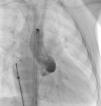

The most frequent symptoms were murmur and/or fatigue. All fistulas were congenital. Five patients (42%) had concomitant cardiac disease: pulmonary atresia with intact ventricular septum (1), patent ductus arteriosus (1), ostium secundum atrial septal defect (1), stenotic bicuspid aortic valve (1), and critical pulmonary stenosis operated in the neonatal period (1). Selective angiography was performed to delineate the anatomy of the fistula(s), which were embolized in the most distal part, sparing all the collateral branches. In one patient an arteriovenous loop was formed through the fistula, embolizing the terminal part of the fistula from the right atrium. The patients were heparinized (100UI/kg in children and 5000UI in adults) and were subsequently monitored by assessing activated coagulation time. Three patients had two fistulas, while the others had a single lesion. All fistulas were hemodynamically significant. They originated in the territory of the right coronary (10), left coronary (3) and circumflex (2), draining into the right ventricle (5), pulmonary artery (6), right atrium (2) coronary sinus (1) and left ventricle (1). Embolization materials included 15 standard coils in three patients, a Jackson® coil in one patient (Figures 1–3), 27 microcoils in 11 patients (18 standard microcoils in seven patients and nine GDC microcoils in four patients), and an Amplatzer® duct occluder in one patient (Figures 4–7). The GDC microcoils, both standard and complex, deserve particular mention, as release of these devices is controlled by electrolysis. The procedure is thus reversible up to the last stage of release, following confirmation of correct positioning. An Amplatzer® cardiac plug was tested in one patient but was not released due to its unsuitability for the lesion.